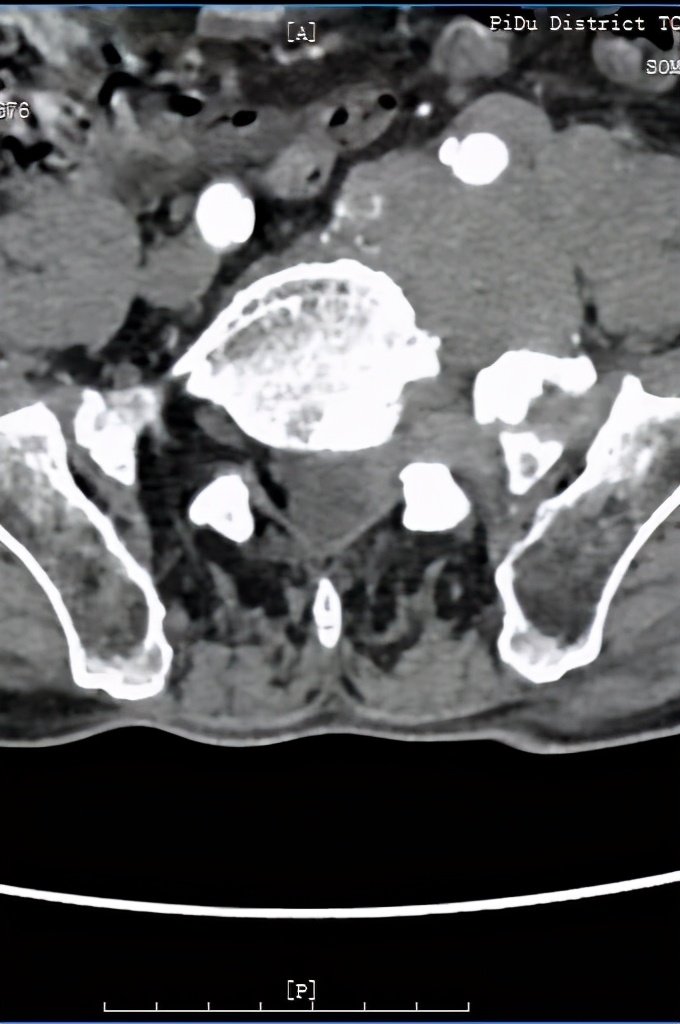

术前CT及MRI检查发现腰5/骶1椎管及左侧神经根管、椎旁软组织肿块